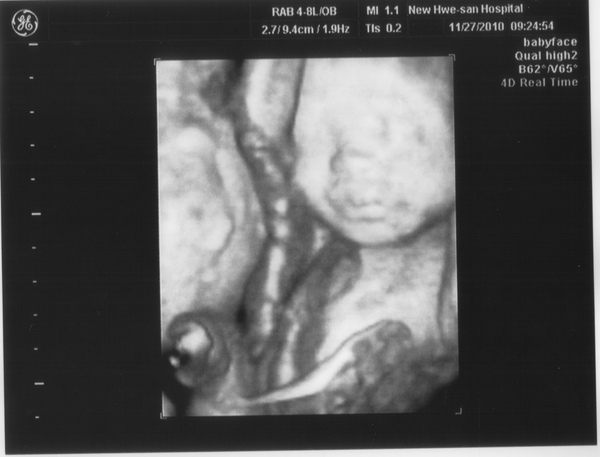

20101209_004.JPG

第二十四週11/23~11/29

檔案大小:

66 kb

尺寸:

600 x 457